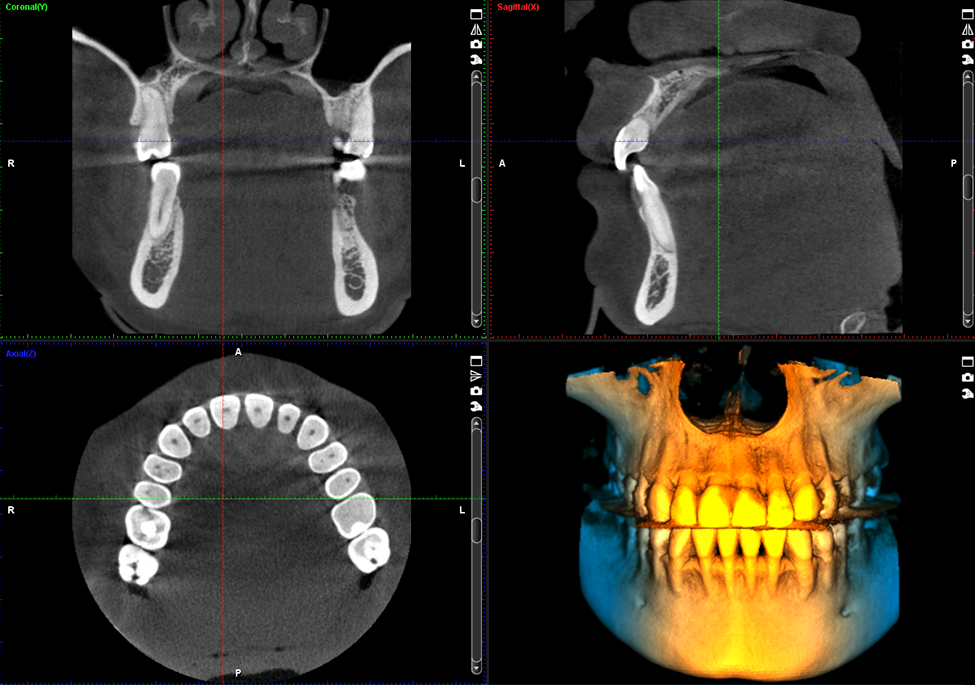

Planmeca ProMax 3D Classic oferuje wyjątkowe możliwości leczenia obszarów o większej średnicy. Maksymalna średnica została zwiększona z Ø80 x 80 mm do Ø110 x 80 mm, co czyni go idealnym do uchwycenia całego zęba w jednym skanie.

Zobacz najdrobniejsze szczegóły

Tryb endodontyczny oferuje niezwykle wysoką rozdzielczość przy rozmiarze voxela 75 µm. Tryb ten jest idealny do wyodrębniania najdrobniejszych szczegółów, umożliwiając dokładną diagnozę i planowanie leczenia.